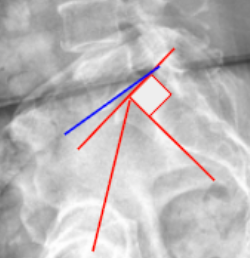

Sacral Slope (SS)

Slip Angle/Lumbosacral Kyphosis

Lumbosacral Angle (Ferguson’s Angle/Sacral Inclination)

Boxall’s Angle (Sacral Inclination)